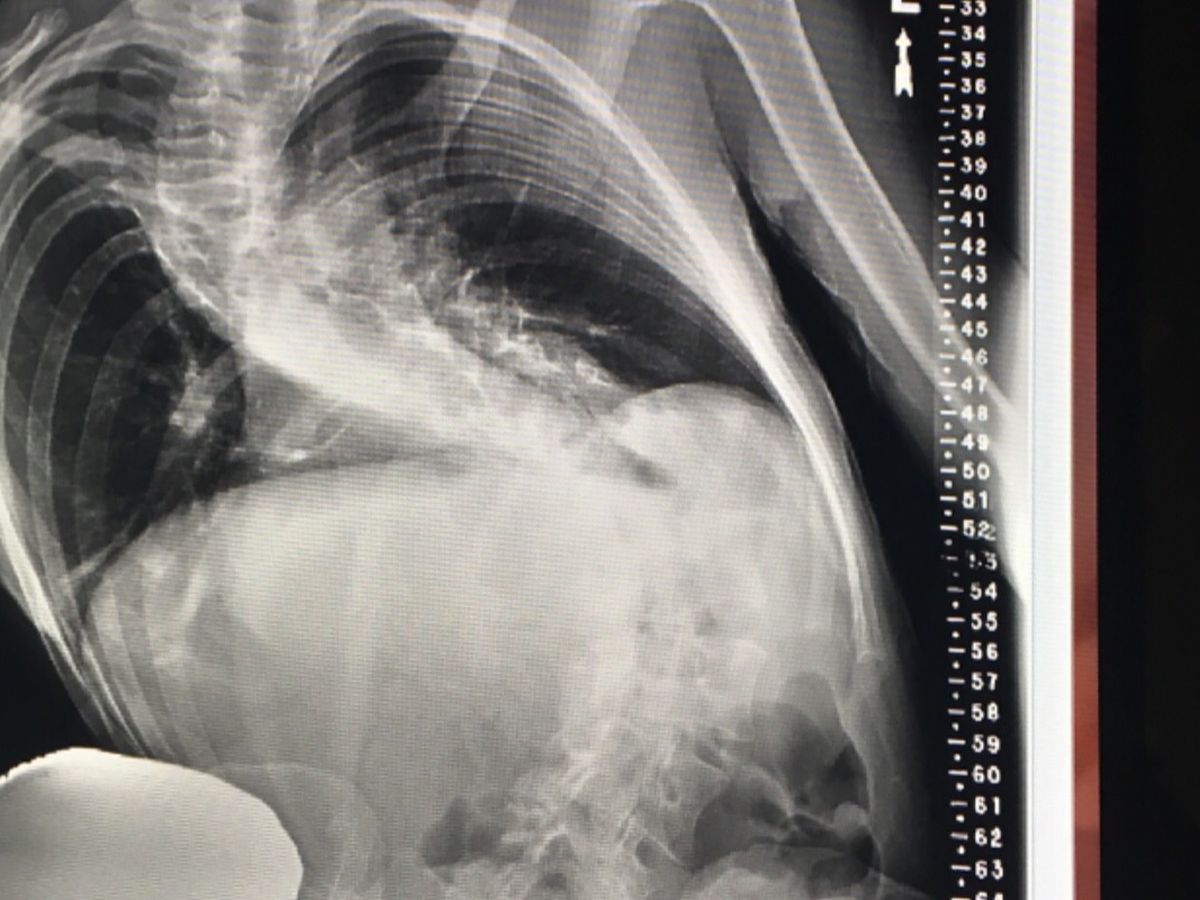

She has only until the end of the year to get limber enough for the one truly beneficial (not all death& paralyzation risksx3!!)treatment program to fit her with a high maintenance bracing system. This goes hand in hand with the Schroth physical Therapy regimen, which is arduous and rigorous to say the least. She is eligible right now, but with multiple areas of spinal fusion, the only means of gaining any ground in this regard, would be to comply with her chiropractors recommendation and go in for subluxation and orthogonal atlas adjustments(as well as ARP wave treatment{electric impulse treatment}) at $75/visit, 3x week.

There’s NO WAY she can afford even 1xweek as it stands, and she is very quickly running out of time. She has always amazed her specialists with her ability to conform to whatever stimuli she is exposed to, “elastica” is what 4 doctors called her over time& in fact, being stuck in a wheelchair for 3 months and being forbidden to engage in stretching/yoga- is what initiated this severe nose dive.

At the end of the year, due to the damage the efforts to get limber will inevitably subject her spine to, if She’s unable to get in to see the therapist frequently enough, the progress will not be substantial enough for Spine-Cor, and neither the terrifying surgical option NOR spine Cor will accept her with more damage to undo. She is already the most challenging case either practice (UCSF/Spine-Cor) has ever been faced with to date.